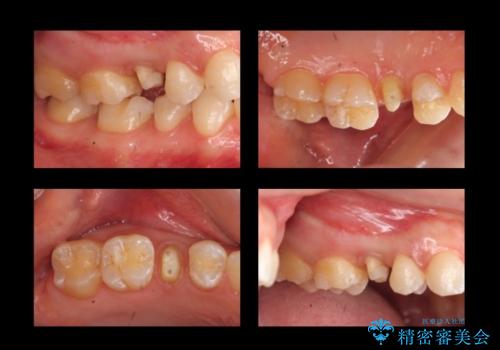

歯の高さがなく、しょっちゅう外れる 他院で治療途中だが病院を変えたい

- 他院で治療途中、歯を被せたら頻繁に外れてしまうとのことでした。

診察すると、歯の高さがなく物理的に外れやすい状態となっていました。

歯周外科治療で歯の高さを出し、外れにくくしました。

高さがなく外れやすいことに関しては、高さを出す以外にないのですが、向かい合わせの歯があるため、被せ物の高さを高くするわけにいきません。